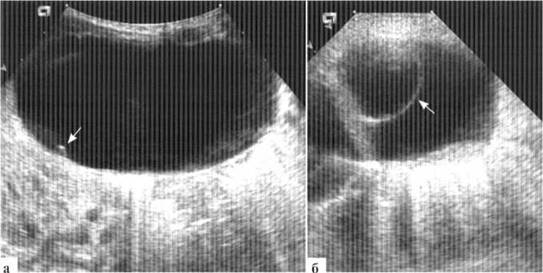

Патогномоничным эхографическим симптомом кисты яичника является наличие мелких пристеночных внутрипросветных кист (рис. 2.2). К сожалению, частота встречаемости этого эхосимптома не превышает, по данным разных авторов, 50—70%. Внутрипросветные кисты могут быть единичными (чаше) или множественным (значительно реже), иметь диаметр от 2 до 10 мм.

Рис. 2.2. Пристеночные внутрипросветные кисты (стрелки) в кистах яичников у новорожденных:

а — единичная мелкая внутрипросветная киста (стрелка) у новорожденной с кистой правого яичника, достигающей 7 см в диаметре;

б — единичная, относительно крупная (10 мм в диаметре) внутрипросветная киста у новорожденной 16 суток с кистой левого яичника до 29 мм в диаметре